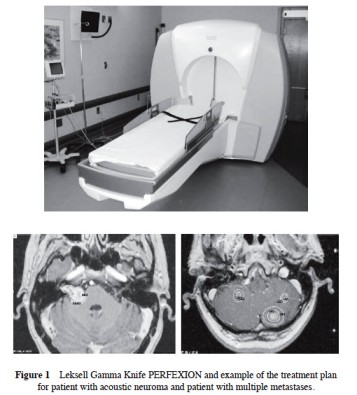

Leksell Gamma Knife (LGK) PERFEXION (PFX) model (Figure 1) is an entirely new design of LGK as compared to other models U, B, C and 4C. The PFX system has 192 Co-60 sources that are fixed on eight sectors. Each sector can be automatically moved independently to five different positions: three positions define collimator sizes (4, 8, 16 mm), off position (sources are blocked) and home position. The machine aperture for the patient’s head during treatment was increased in volume by more than three times resulting in a greater mechanical treatment range in X/Y/Z stereotactic coordinates. The Automatic Positioning System responsible for stereotactic coordinates setting was replaced by a Patient Positioning System that moves the whole robotic couch with patient body to pre selected stereotactic coordinates improving patient comfort and efficiency of the treatment. This study describes four years experience from the University of Pittsburgh Medical Center and two years experience from Na Homolce Hospital with this new radiosurgery system. Study compares and evaluates dosimetry, treatment planning, treatment efficiency, accuracy and overall performance of this new gamma knife system.